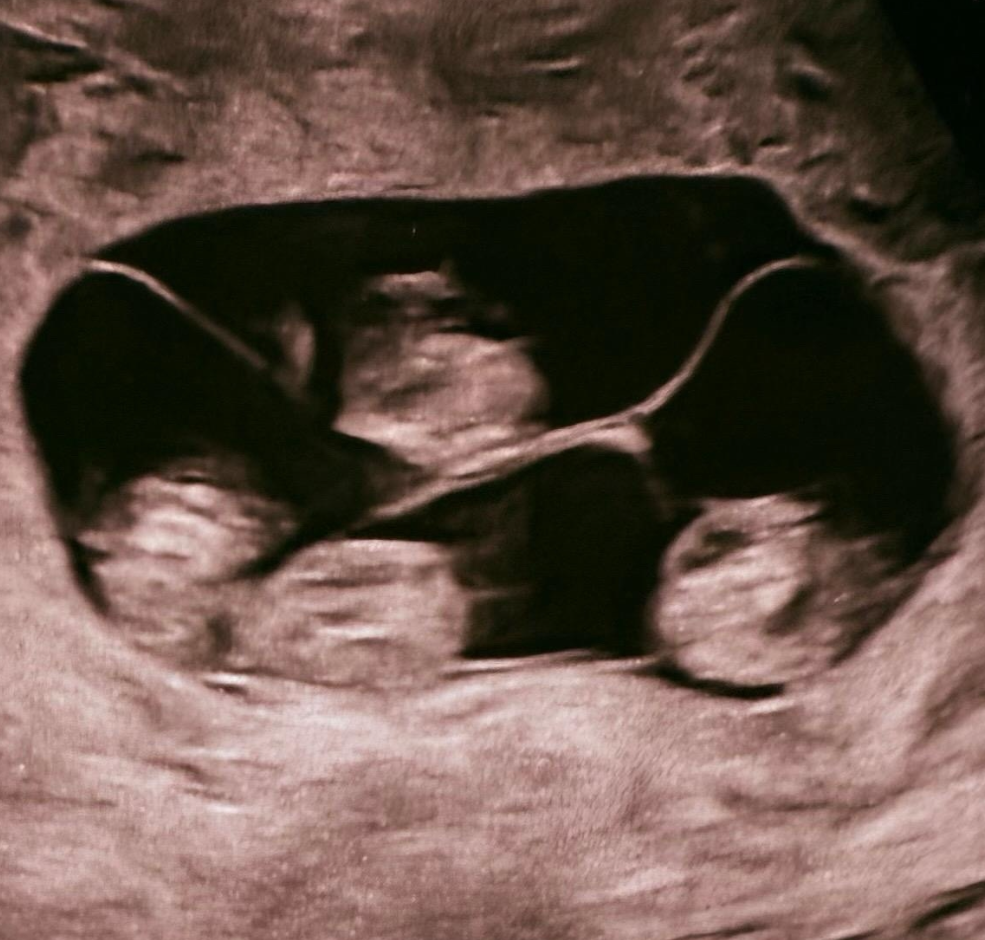

Монохориальная беременность — подвид однояйцевой беременности. Ее главная особенность в том, что все эмбрионы делят одну общую плаценту (хорион). Из-за общей сосудистой системы плаценты такие беременности считаются высокорисковыми и требуют частого УЗИ-мониторинга (каждые 1-2 недели).

Также выделяют биамниотическую (каждый плод развивается в своем собственном амниотическом мешке (плодном пузыре), разделенном перегородкой) и моноамниотическую (зародыши развиваются в общей амниотической полости) беременности.